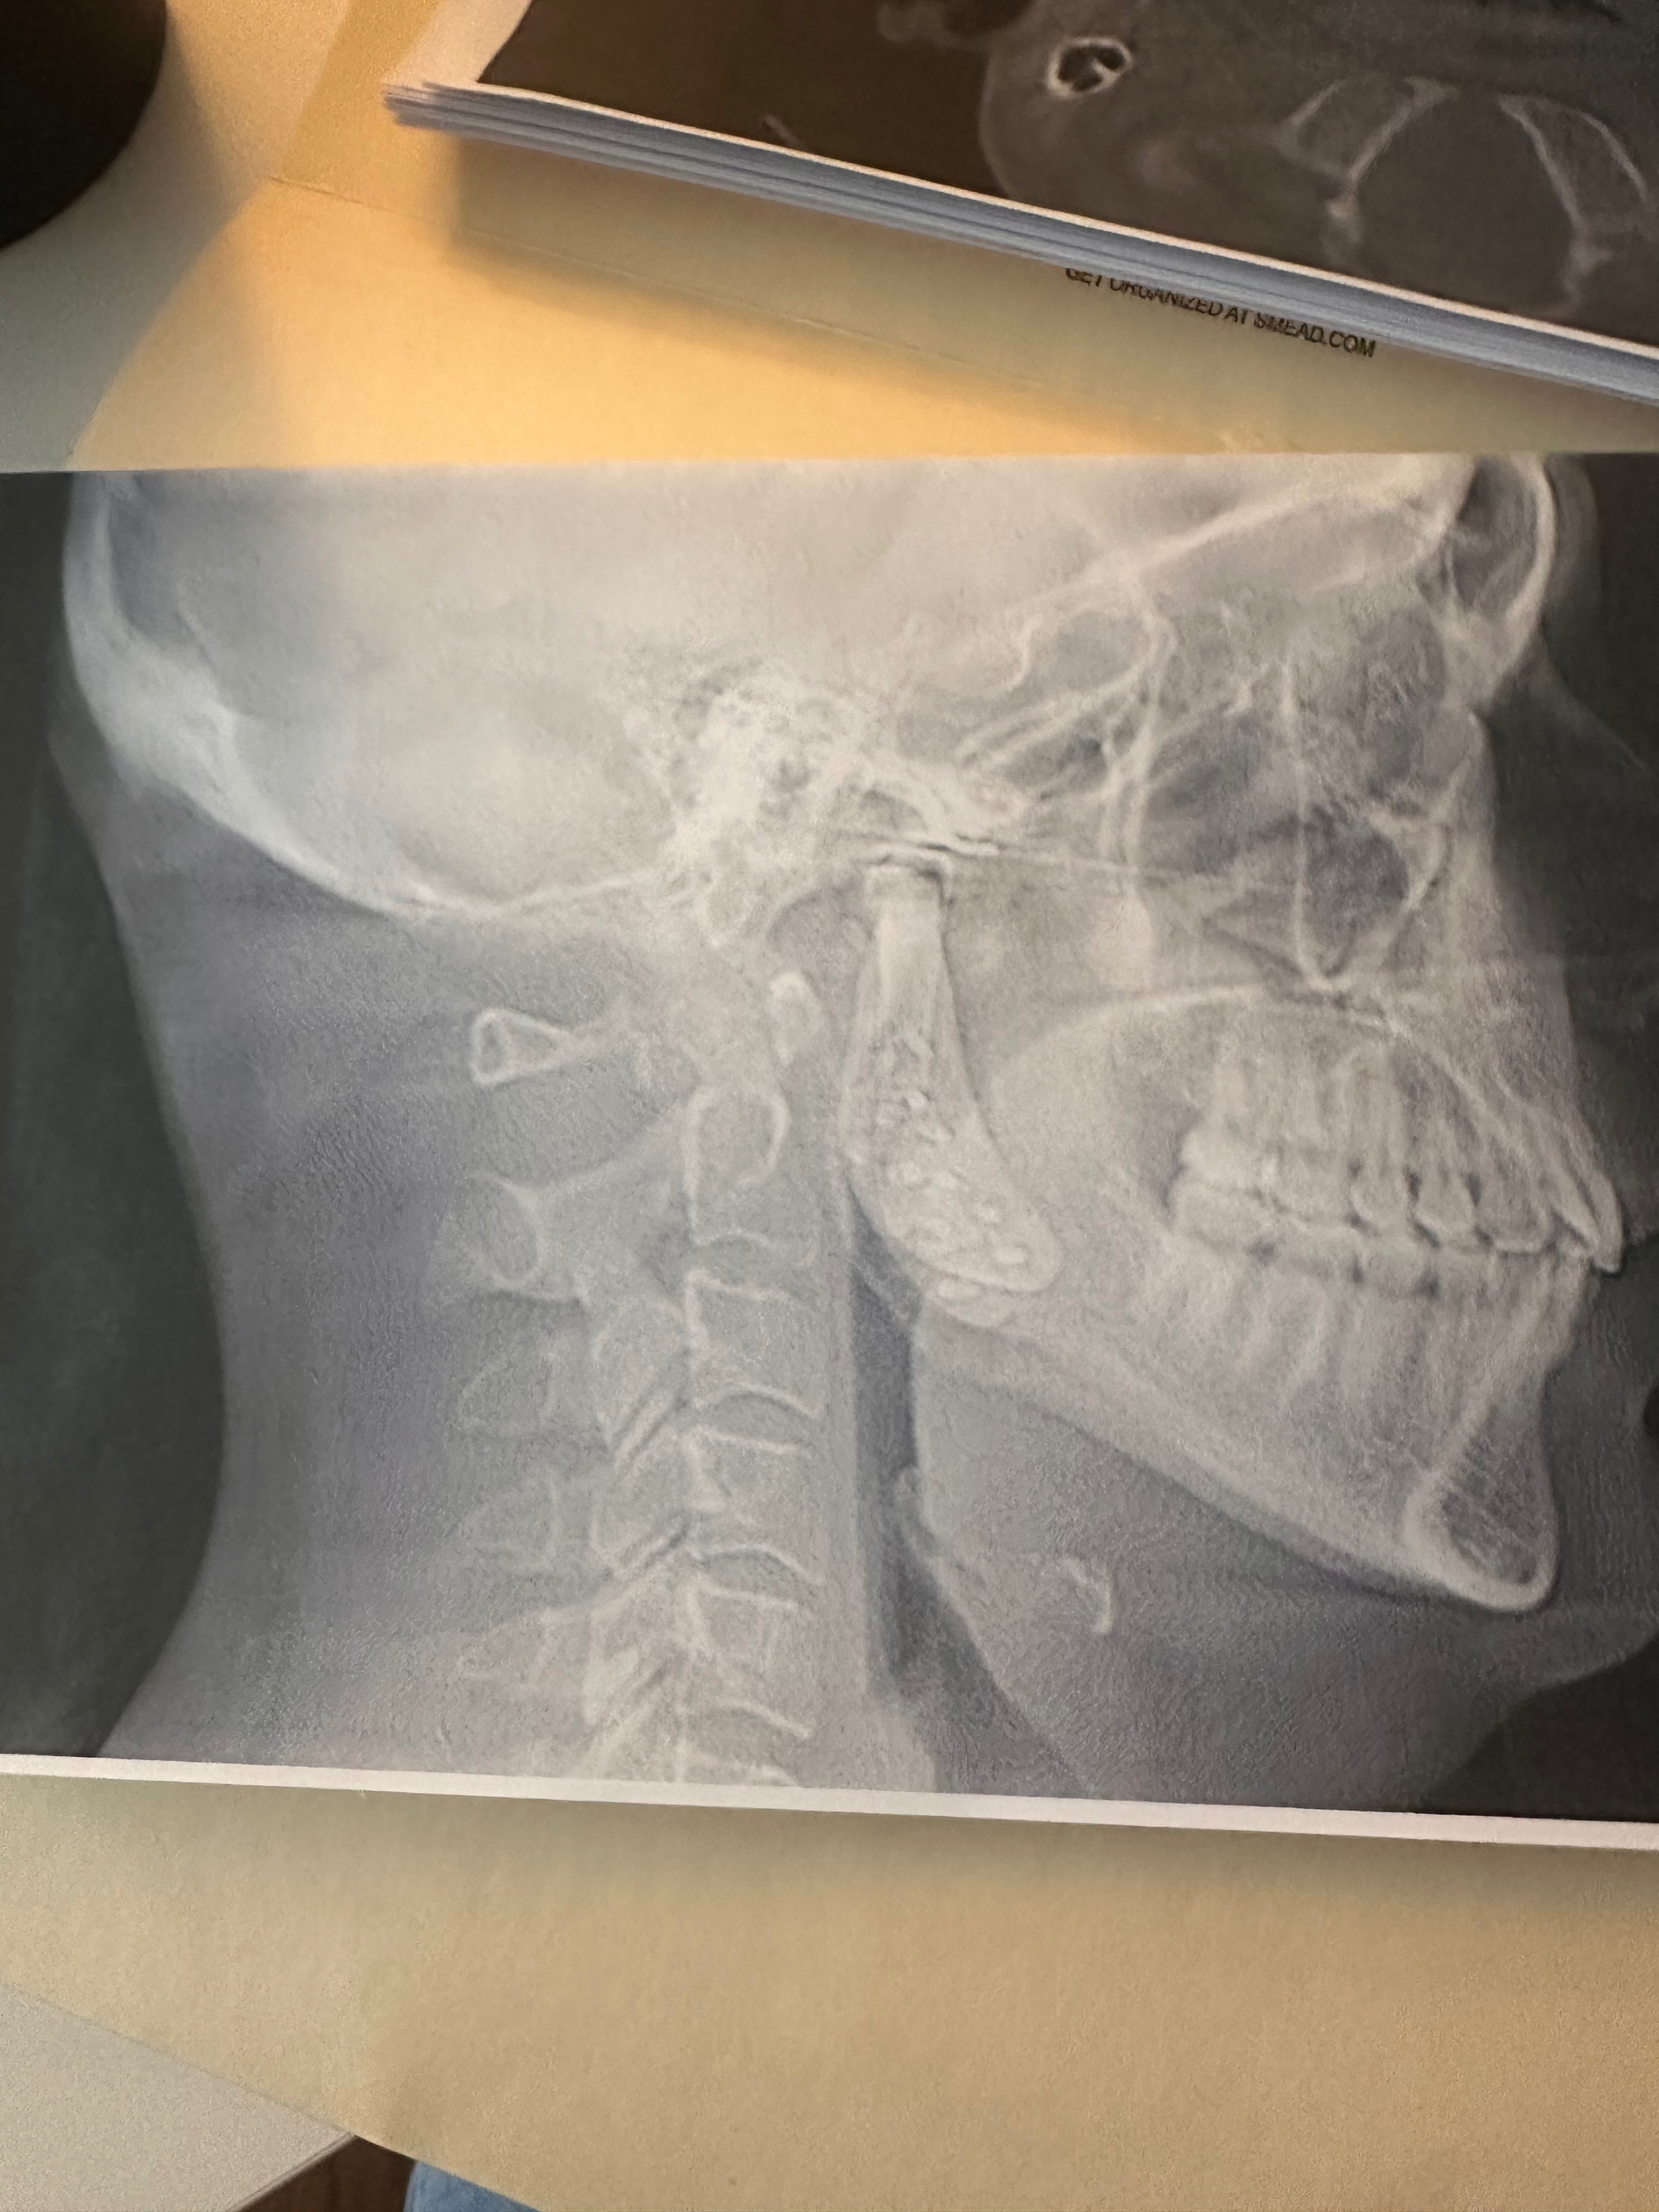

In 2022, I finally found a TMJ specialist who discovered a tumor in my jaw joint. He explained I needed complex reconstructive surgery: removing extra bone, moving my jaw forward, opening my airway, and properly placing prosthetic joints. I could not afford it at the time.

In 2023, the military removed the tumor and placed prosthetic joints, but did not correct the underlying structural issues. My jaw wasn’t fully advanced, the extra bone was still there, my airway remained narrow, and I still experience severe pain and difficulty eating, talking, and even breathing.

CT Evaluation (3D mapping for precise prosthetic placement)

Cone Beam CT Scan (High-detail imaging to guide surgery safely)